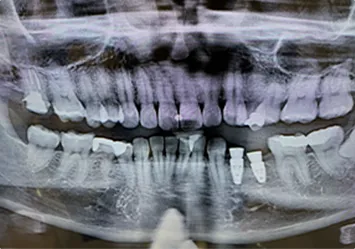

CASE 01

治療前

治療前写真 恵比寿南DENTAL 治療前写真 恵比寿南DENTAL 治療前写真 恵比寿南DENTAL

施術内容

【40代女性】

右上の前歯が歯根破折となっしまった為抜歯を行い、抜歯と同時にインプラント埋入を行った

治療期間

3ヶ月

リスク

術中の不可抗力によるトラブル(出血など)、術後注意事項を守らないことによる疼痛、感染、上部構造装着後口腔内清掃を怠ったことによるインプラント周囲組織の炎症

副作用

治療後の口腔内清掃、及びメインテナンスを怠ったことによるインプラント周囲粘膜炎またはインプラント周囲炎

費用

インプラント埋入:30万円

ジルコニアオールセラミッククラウン:15万円